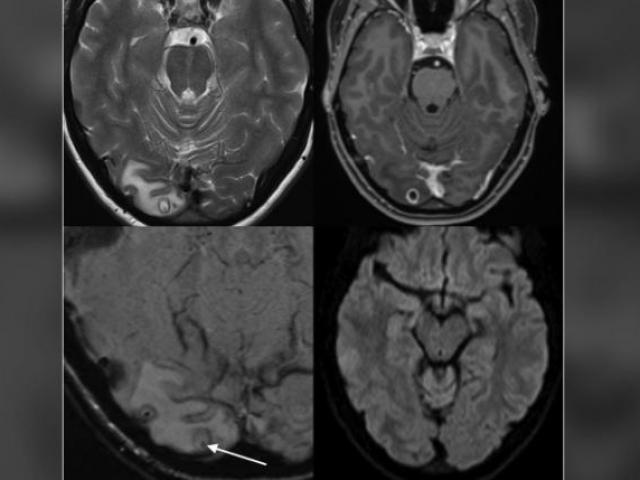

"Những cục u to màu trắng trên tay chân Tiểu Hải là hạt tophi, triệu chứng nghiêm trọng của bệnh gout", bác sĩ Trịnh nói.

"Kết quả kiểm tra cho thấy hàm lượng axit uric trong người Tiểu Hải rất cao, lên tới 900umol/l. Chúng tôi lập tức thực hiện các phương pháp điều trị chống viêm và hạ axit uric. Hiện đã tạm thời ổn định mức axit uric trong máu của cậu ấy xuống 400umol/l, Tiểu Hải đã dần đứng được và di chuyển. Trong quá trình tiếp theo, chúng tôi sẽ tiếp tục tích cực giảm axit uric cho cậu ấy, đồng thời cố gắng chữa trị để các hạt tophi trên khớp tiêu dần hoặc thậm chí biến mất", bác sĩ Trịnh chia sẻ.

Các khớp tay sưng cục đáng sợ của Tiểu Hải.